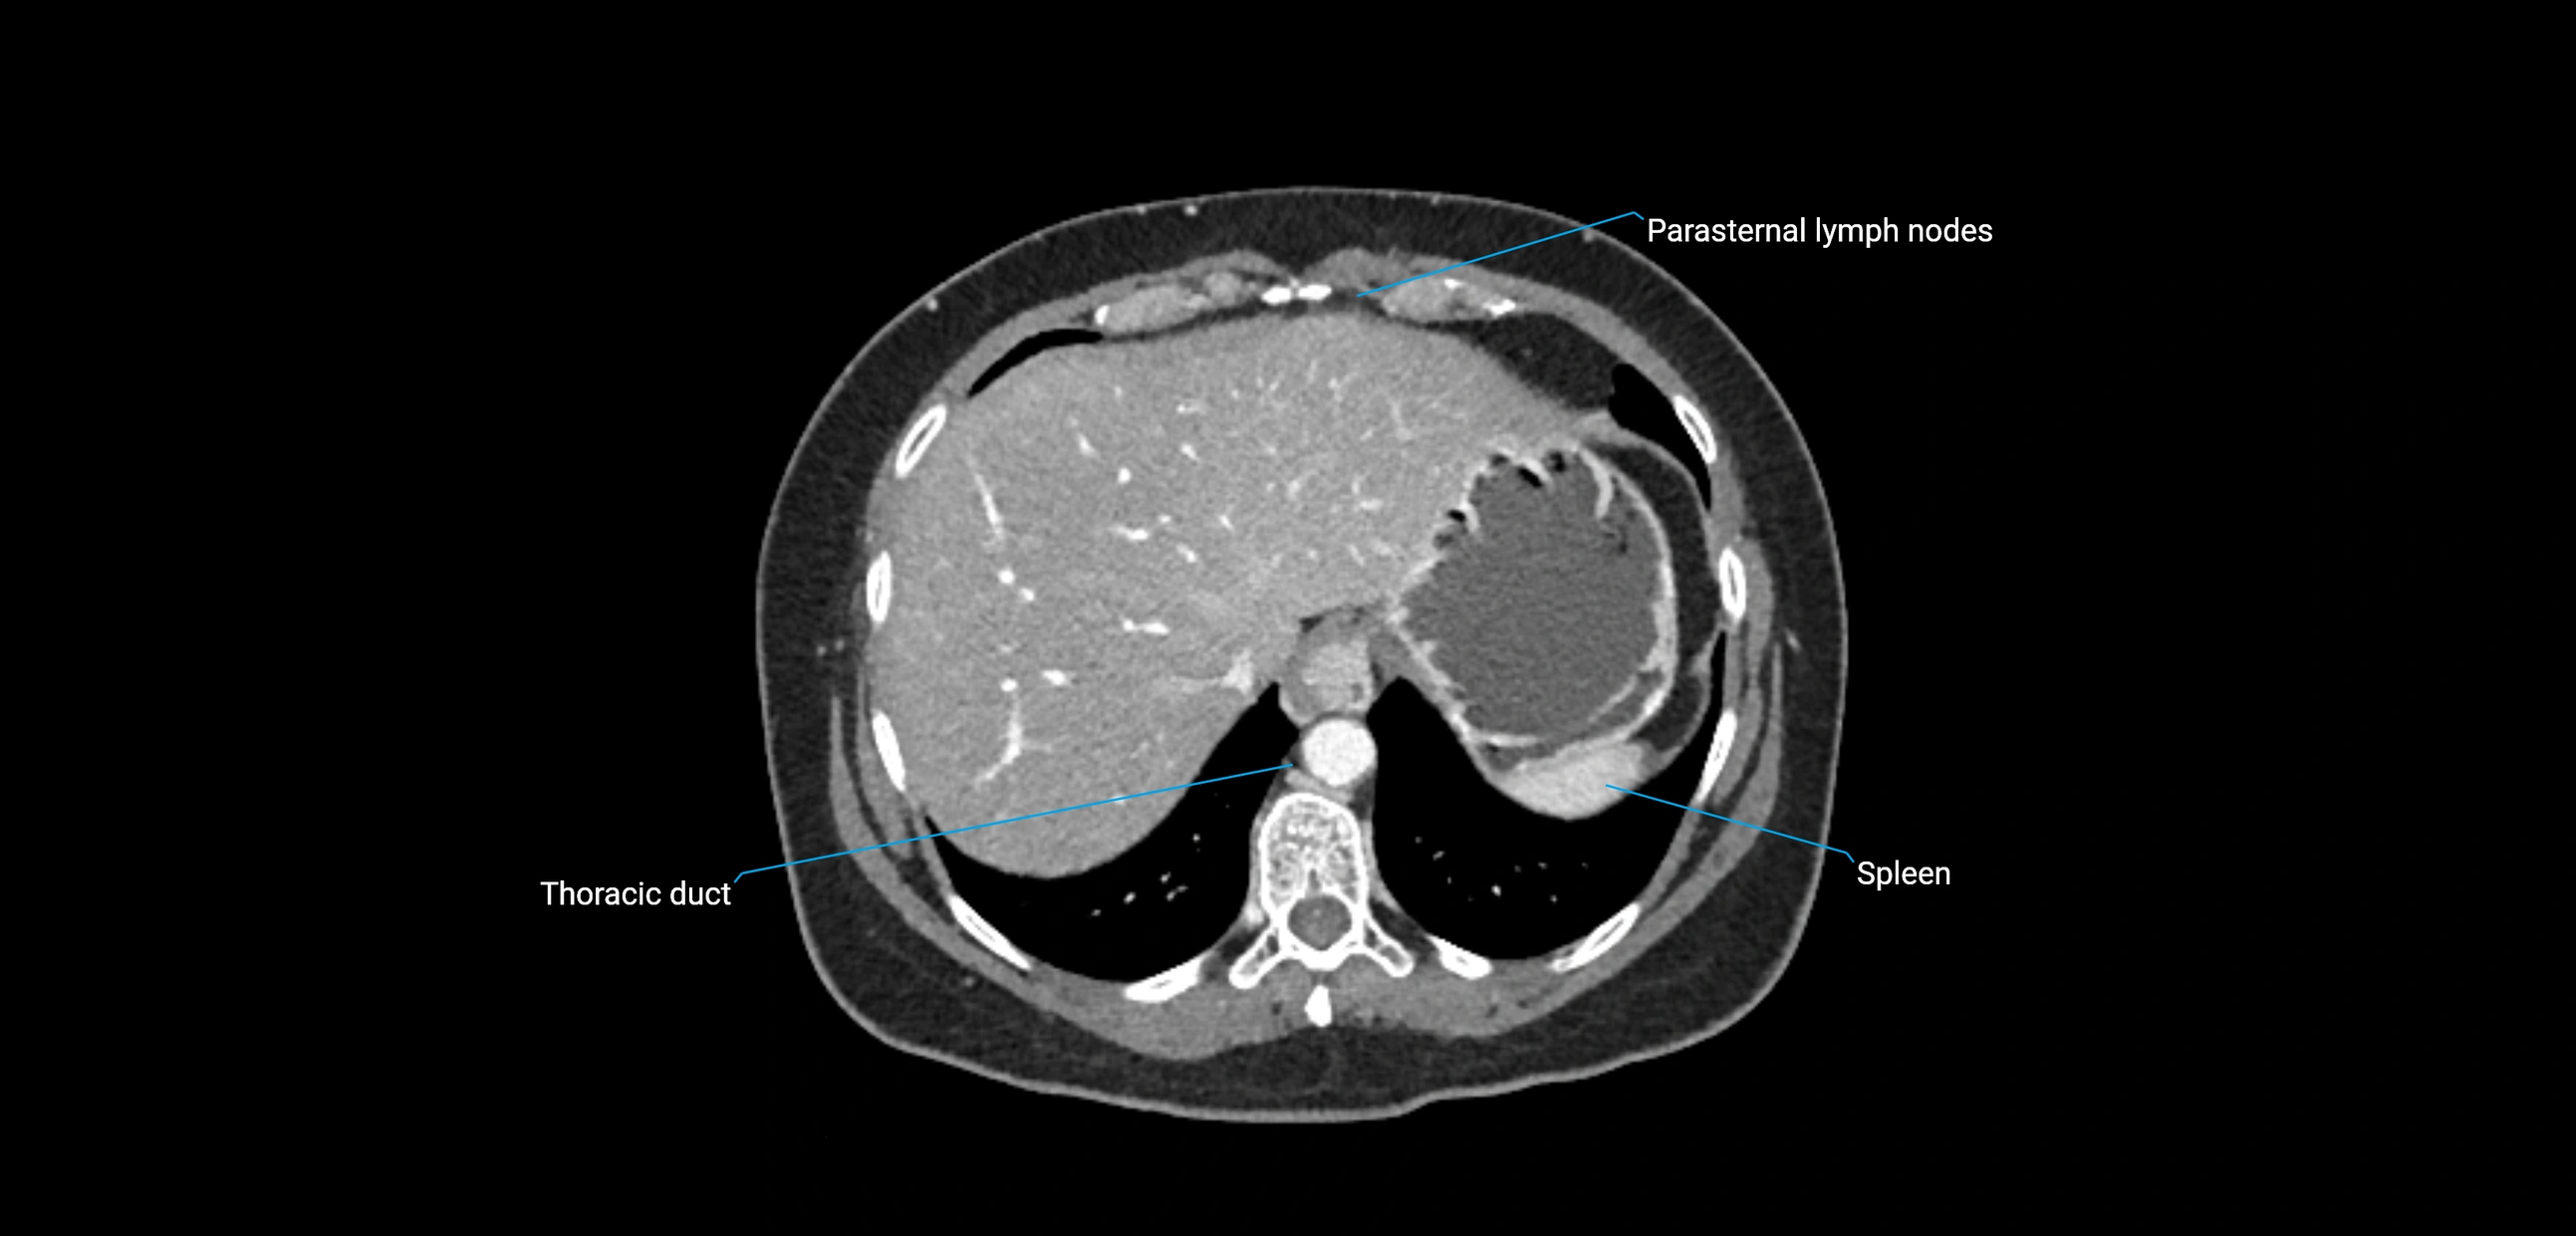

CT image

image